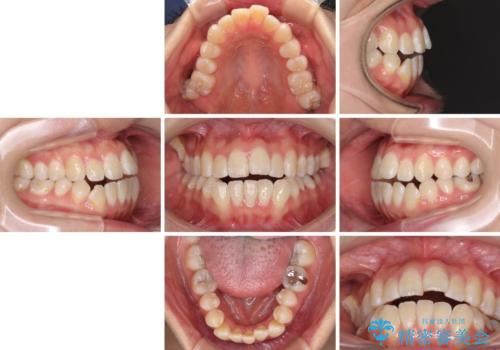

- 上下前歯の隙間と、外側を向いていて歯磨きのしにくい奥歯を気にして来院された患者様です。

下顎前歯が1本欠損しており、上下アーチはアンバランスとなりますが、インビザラインを用いて上下の隙間を改善しながら歯列を整えることとしました。

外側を向いている奥歯は、内側にアンカースクリューを埋入して牽引の固定ゲント氏、部分的にワイヤー装置を用いることで歯列に納めることとしました。

下顎前歯の1本欠損により左右の咬合が不安定となり、治療経過で噛みにくい状態が続きましたが、最終的には違和感なく噛めるようになりました。